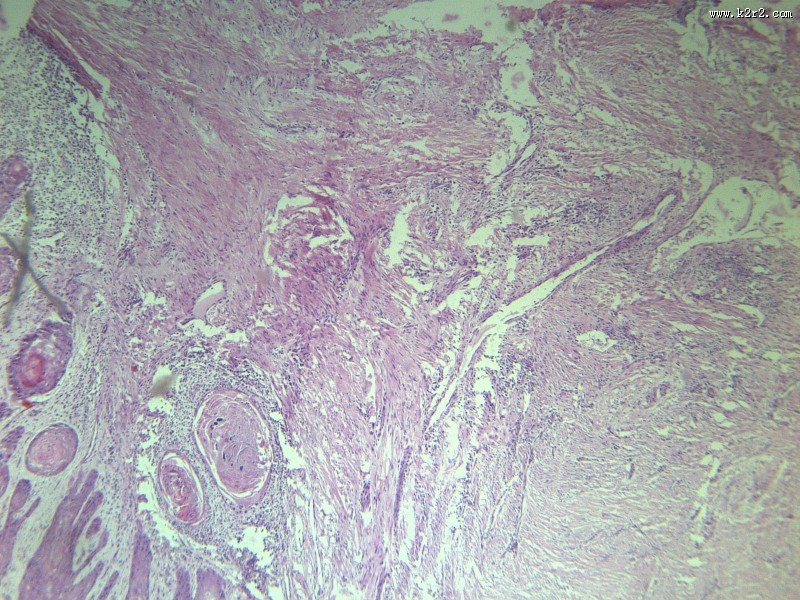

首页 > 其他类别 > 高分化鳞癌(12张) > 高分化鳞癌 第9张

高分化鳞癌 - 第9张